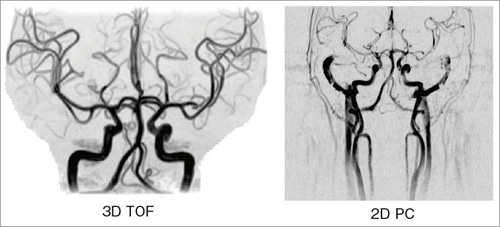

頭部MRA

頭部MRAの撮像法を表1-(2)に,画像を図3に示す。3D TOFは,MTCパルスを付加することにより,末梢までの血管が明瞭に描出できる。また,3-slabで撮像するが,slabとslabの間は信号差がほとんど目立たず,まるで1-slabで撮像したかのように見える。図4の症例では,瘤から出ている細かい血管まで,はっきりと描出されているのがわかる。

図3 頭部MRA